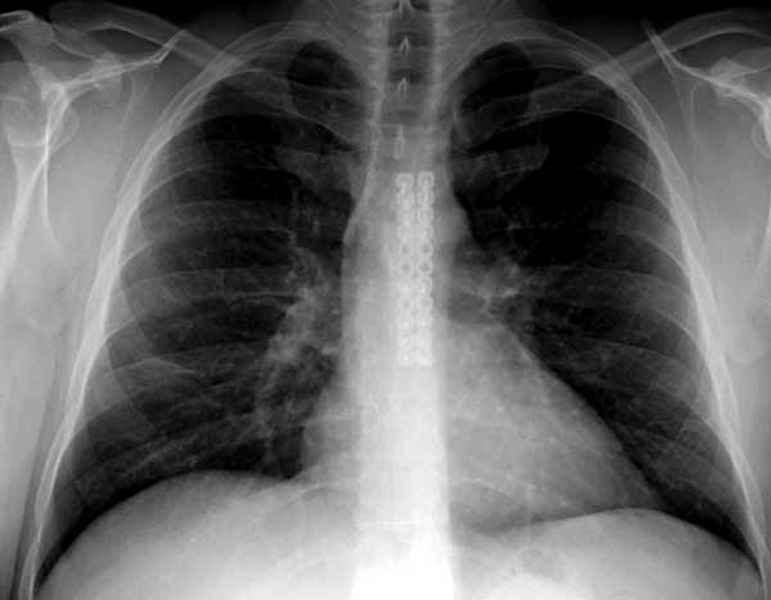

как бы не закончилось келлоидом. Помоему на рентгене грудинно-ключичное

сочленение с заинтерессованной стороны отличается от здорового - это

могло быть последствием доступа или интраоперационной травматизации,

Имя     : sternum ap.jpg

Имя     : 3 Nonunion sternum ap.jpg